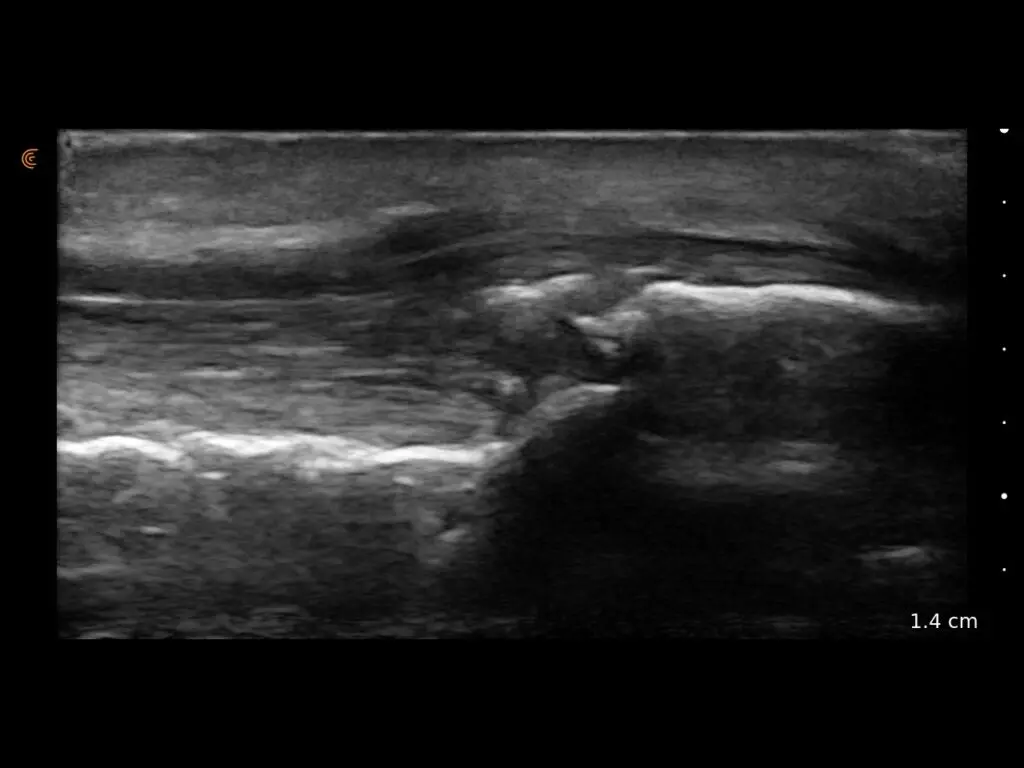

ProbeFix Dynamic is a new device that enables high-quality ultrasound measurements during dynamic exercise by keeping an ultrasound probe in place, allowing for muscle monitoring during intense movement and creating new research possibilities in muscle imaging.